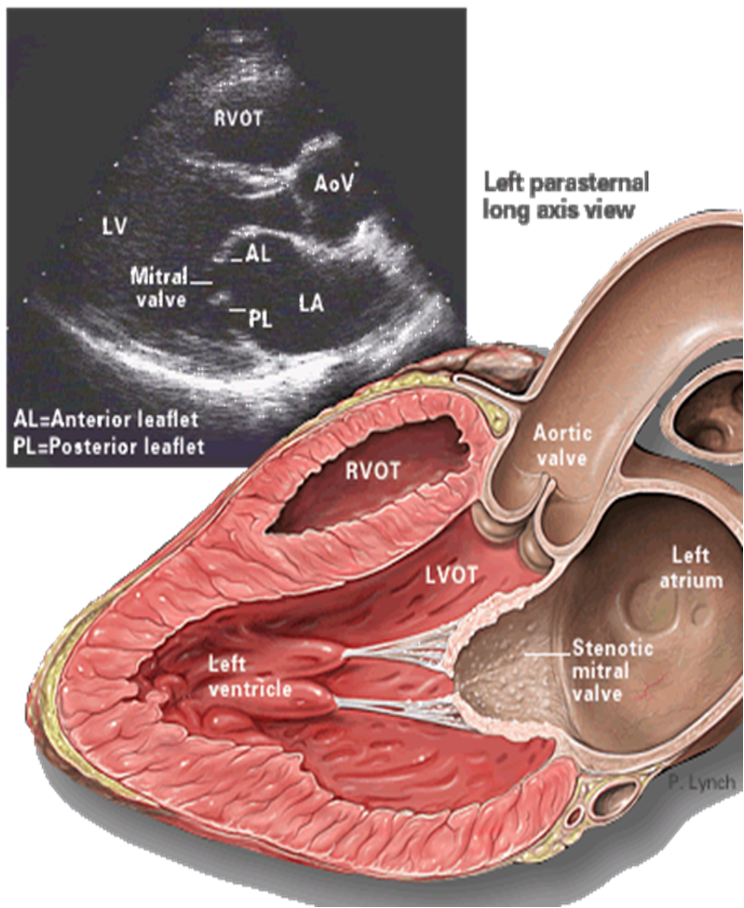

- TTE (Transthoracic echocardiography): best initial test to evaluate the mitral valve and quantify the anatomical extent of the stenosis.

Findings-

Reduced mitral valve area (MVA): ≤ 1.5 cm² (severe)

-

Thickened, calcified leaflets with commissural fusion

Increased mean diastolic pressure gradient across the mitral valve

RV dilation

LA enlargement

Evidence of pulmonary hypertension

- TTE is the most important test for diagnosing and guiding the treatment of mitral stenosis.